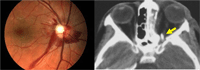

El traumatismo indirecto puede lesionar la porción anterior nervio óptico (avulsión o rotura del fascículo), o la posterior. Esta última es más frecuente y se acompaña de fondo de ojo normal en fase inicial. La TC orbitaria y craneal permite detectar fracturas o lesiones susceptibles de tratamiento (hematomas subperiósticos o de la vaina del nervio óptico) (Figura 6).

Figura 6. Neuropatía óptica traumática (izquierda). TC orbitaria (derecha): fragmento óseo libre intraconal